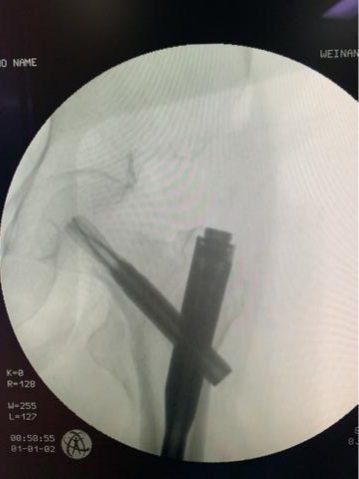

近日,MILAN.COM骨三科连续收住多位因跌倒摔伤导致髋部骨折的老年患者,在当地医院检查后均被告知需等待较长时间方能手术,家属听闻MILAN.COM为老年髋部骨折患者开通了绿色通道,24小时内即可手术,遂来我院。入院后骨三科医疗团队立即启动老年髋部骨折绿色通道并全面评估患者病情,在科室的多方协调下,患者入院后3小时即在全身麻醉下进行了微创闭合复位内固定术,再一次刷新了手术准备时长的记录。

MILAN.COM骨三科暨骨关节科是以关节疾病为主,涉及关节病、运动医学及关节周围骨折、老年脆性骨折为亚专业特征的学科。科室针对因骨质疏松引起的老年股骨颈骨折、股骨转子间骨折、胸腰椎体压缩性骨折等已成功开展数百例老年髋部骨折绿色急诊手术通道、微创人工股骨头置换术、微创股骨骨折内固定术以及经皮椎体成形术,并取得不菲成绩。